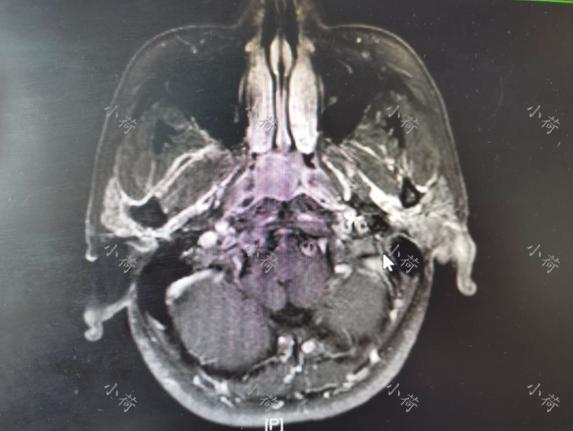

他有半年多的时间鼻涕回吸带血,量不大,略频繁,无其他不适症状,无贫血,因为这次鼻出血,在我建议下,过来检查,在门诊做了鼻咽部MRI(图1),并做了纤维鼻咽镜检查,取了活检,确诊为鼻咽癌。患者还有高血压病史,目前血压控制稳定。入院时,病理结果已经出来,诊断为鼻咽癌,高血压Ⅱ级。

图1 鼻咽部MRI显示局部病变